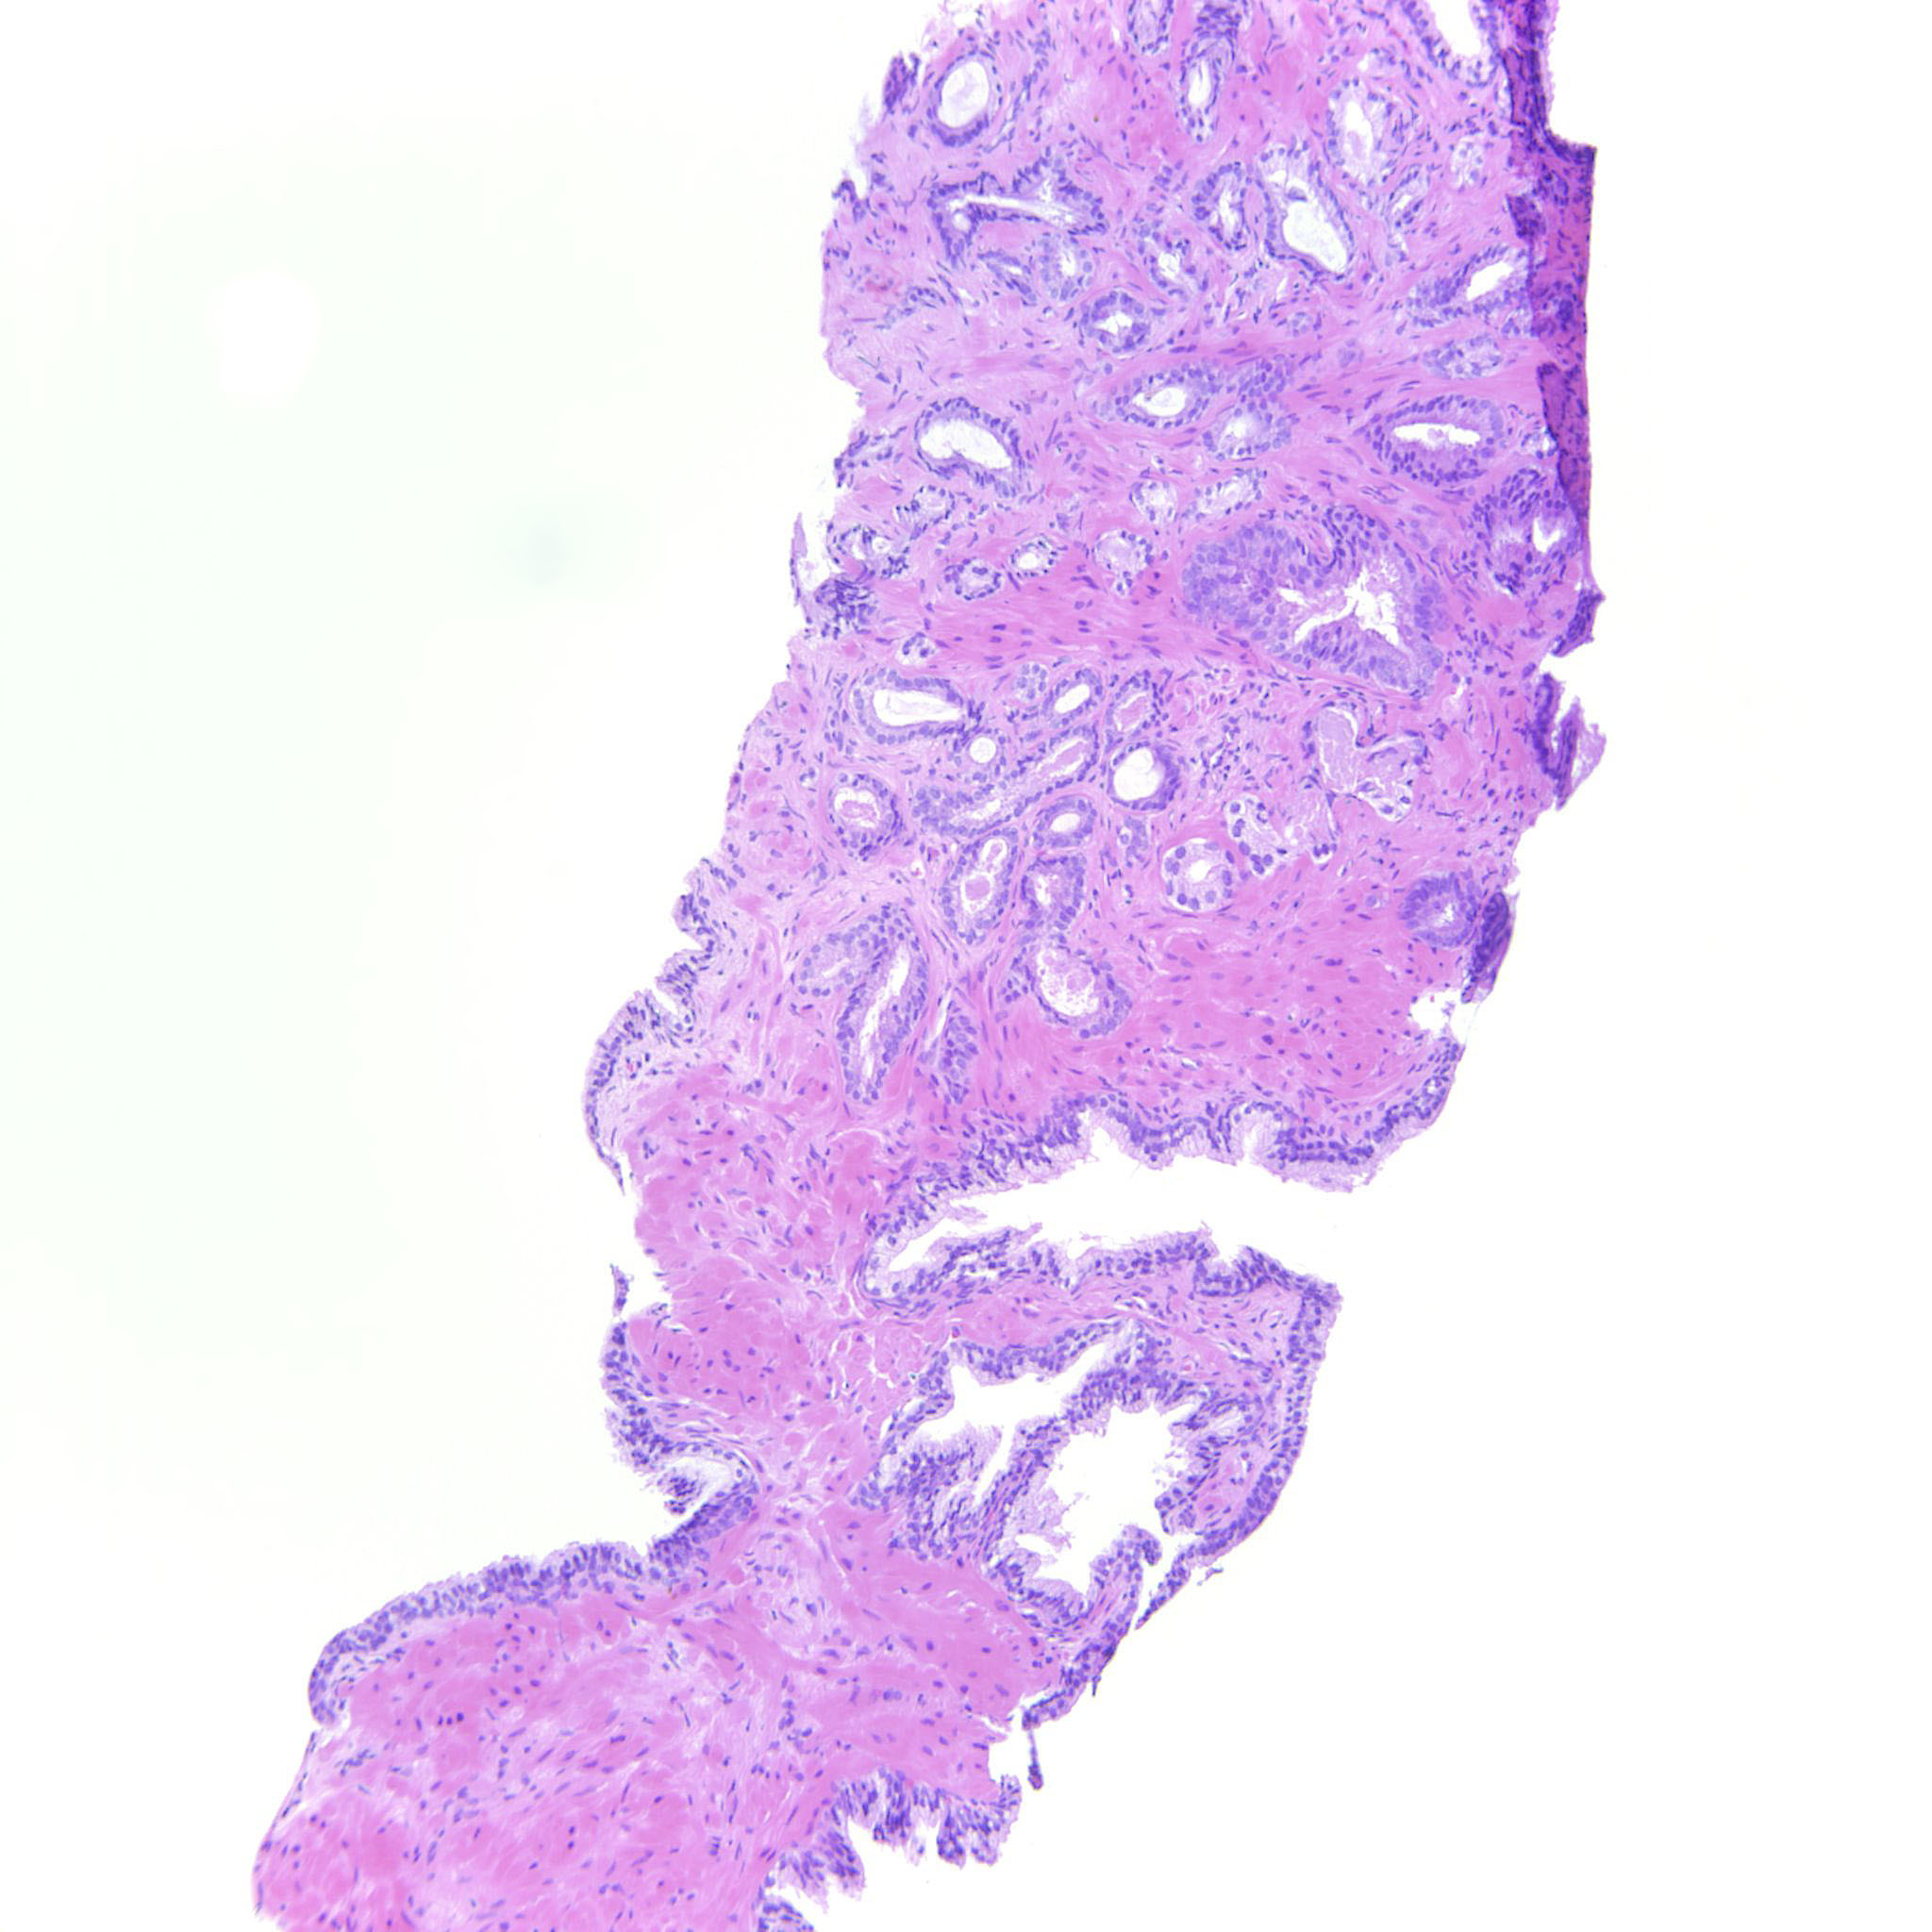

Prostate cancer grading

Case ID: 314